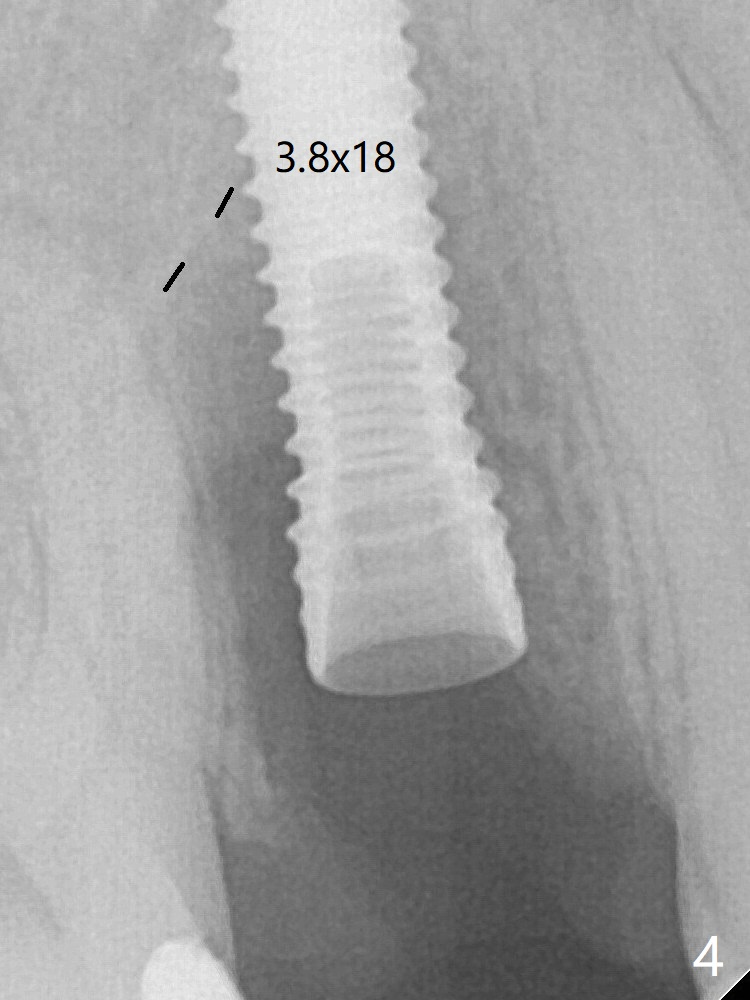

A 3.8x18 mm (definitive) implant is placed with <40 Ncm with the implant plateau apical to the lingual crest (Fig.4 (dashed line: upper border of the buccal defect)). The buccal plate defect is repaired by Vanilla Graft (Fig.6 *) before and after insertion of a 4.5x4(3) mm abutment. The buccal plate defect seems to being repaired 4 months postop (Fig.7).